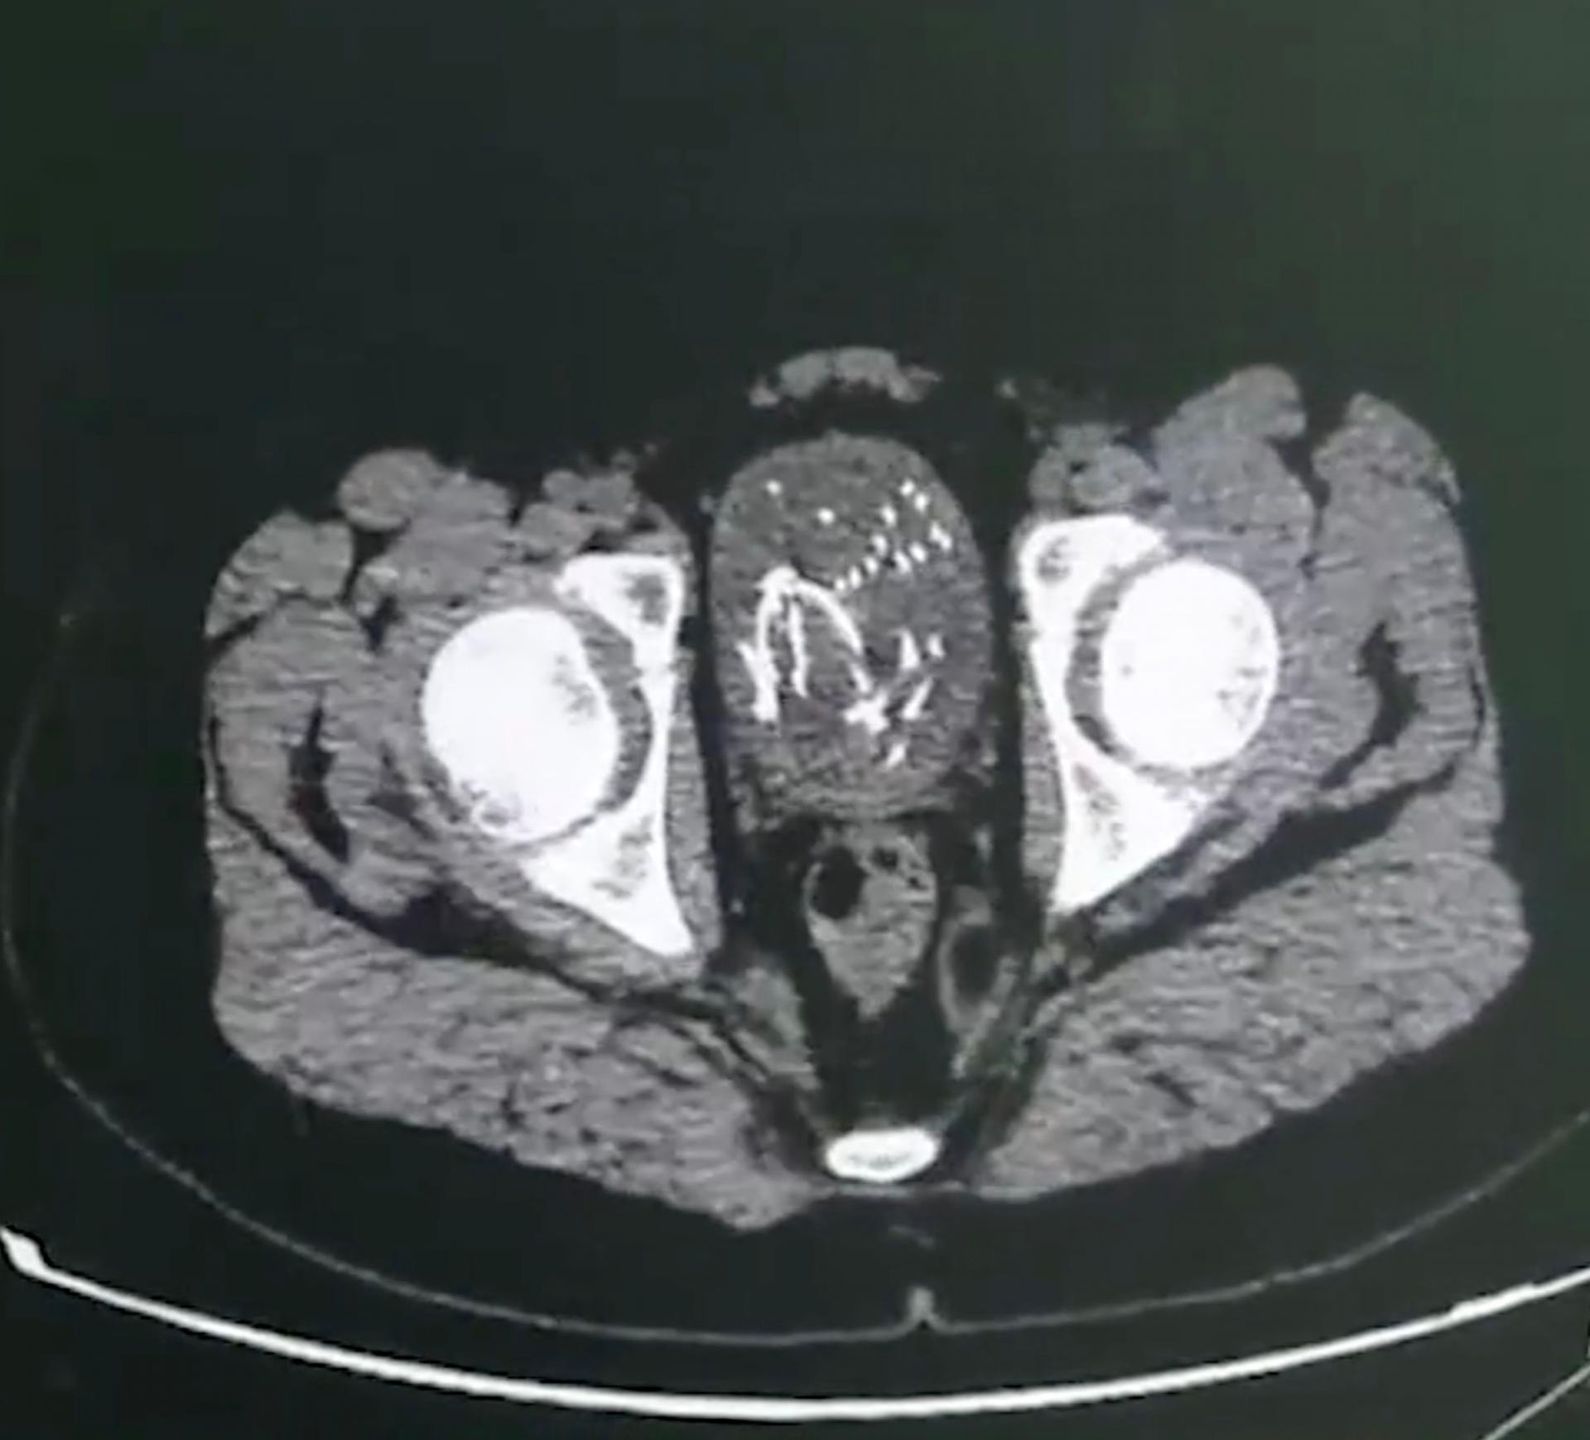

Operacja musiała być wyjątkowo precyzyjna, by nie uszkodzić narządów wewnętrznych dziecka. Lekarze wykonali niewielkie nacięcie w skórze i za pomocą specjalnych szczypiec wyciągnęli przewód z organizmu dziecka. Okazało się, że kabel ma 1,5 metra długości. Będąc już w pęcherzu, zaplątał się, co wywołało infekcję organu.

Kabel w pęcherzu dziecka